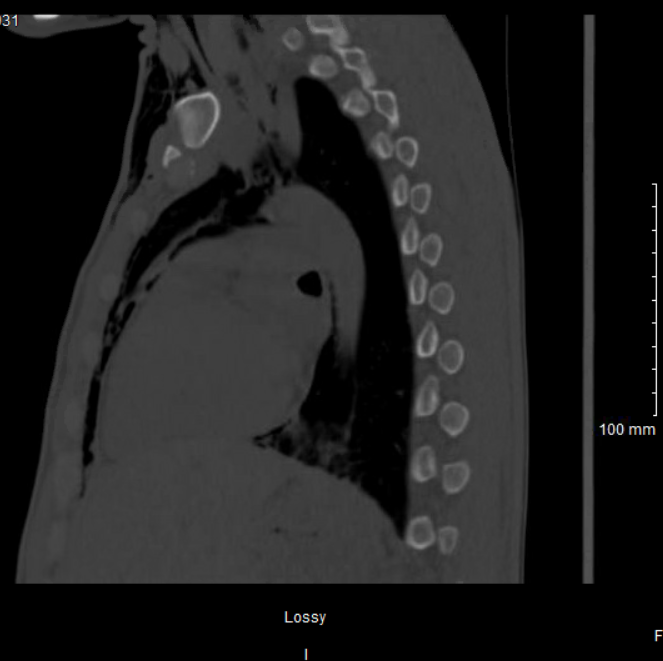

Case Presentation: A 32-year-old male with a past medical history of COVID-19 infection, type 1 diabetes mellitus, repeated episodes of diabetic ketoacidosis (last 6 days prior), S. aureus bacteremia, rhinotillexomania, and medical non-compliance presented with acute onset facial and neck swelling and pain. On admission, a CT of the facial bone demonstrated extensive soft tissue emphysema of the face and a fracture of the right lamina papyracea. The patient denies any history of trauma, chest pain, shortness of breath, or drug use. A chest x-ray shows extensive subcutaneous emphysema with pneumomediastinum and pneumopericardium, new compared to a chest x-ray completed 5 days prior. A CT esophagogram showed no evidence of barotrauma and the interval development of the right lamina papryacea fracture from a head CT one month prior, our team suggested the air within the soft tissues is attributed to the ethmoid fracture and exacerbated by repeated nose blowing. His condition was conservatively managed with sinus precautions, and continuation of his current course of antibiotics for his bacteremia. Repeat chest x-ray and CT chest after 3 days of admission showed improvement, and the patient was discharged on day 4.

Discussion: Subcutaneous emphysema (SE), pneumomediastinum (PM), and pneumopericardium (PC) can occur due to a myriad of different etiologies. Defined as air introduced into the fascial planes, SE can be traumatic, surgical, iatrogenic, or spontaneous in onset. Typically, a perforation within the gastrointestinal or respiratory tract complicated by emesis, coughing, or Valsalva maneuver results in air forced into the subcutaneous tissues, pericardium, mediastinum, or retroperitoneal space. More rarely, air descends from maxillofacial structures causing these pathologies. This patient’s complicated clinical picture reveals multiple potential etiologies for his triad of clinical findings. There are reports of PM and spontaneous SE as a rare complication of diabetic ketoacidosis. [1] Typically resulting from alveolar rupture secondary to changes in pressure gradients from vomiting and/or Kussmal respirations allowing air to move along the bronchovascular bundle. [2] This patient also has a history of medical non-compliance and is a known poor historian, so we cannot completely rule out trauma to the face or cocaine use, which have also been associated with PM. [3]

Conclusions: This case describes a rare triad of clinical findings which may arise in hospital medicine settings as a delayed result of facial trauma. Most likely, this patient’s repeated digital manipulation of the nose caused erosion, followed by fracture to the medial lamina papyracea, a fragile bone on the medial orbital wall. [4] Rathore, et. al reports a case of medial orbital wall erosion secondary to rhinotillexomania complicated by MSSA infections to the soft tissue in the medial orbit. [5] Fractures of the medial orbital wall and ethmoid sinus are more frequently associated with SE than other fractures of the midface. [6] The fracture acts as a ball-valve mechanism, trapping air within the fascial layers. This patient has been known to repeatedly blow his nose as part of his rhinotillexomania, which has been shown to force air into the subcutaneous tissues in the setting of maxillofacial injuries. [7]